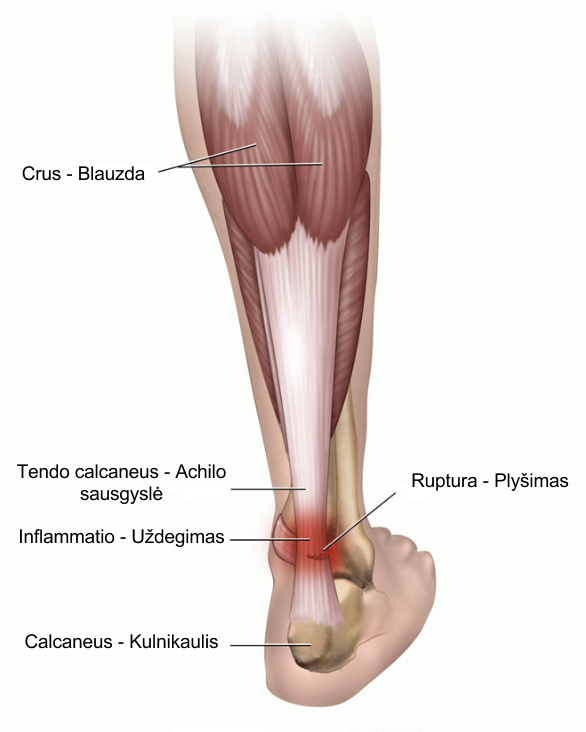

Тендинит Ахиллова сухожилия: симптомы и лечение

Раздел: Картинки на заметку